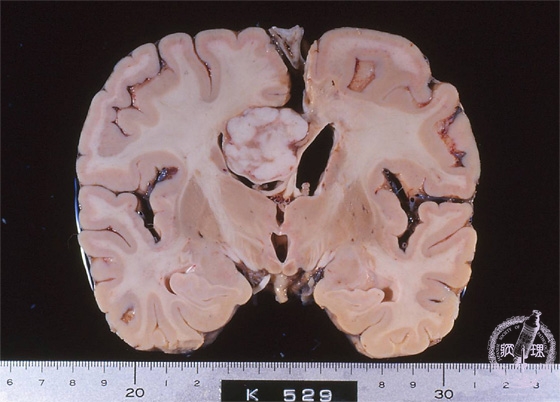

- ★(9)Meningioma

Macroscopic findings: Meningioma arising in the cerebral falx (red circle). The well-circumscribed whitish tumor compressed right lateral ventricle downword